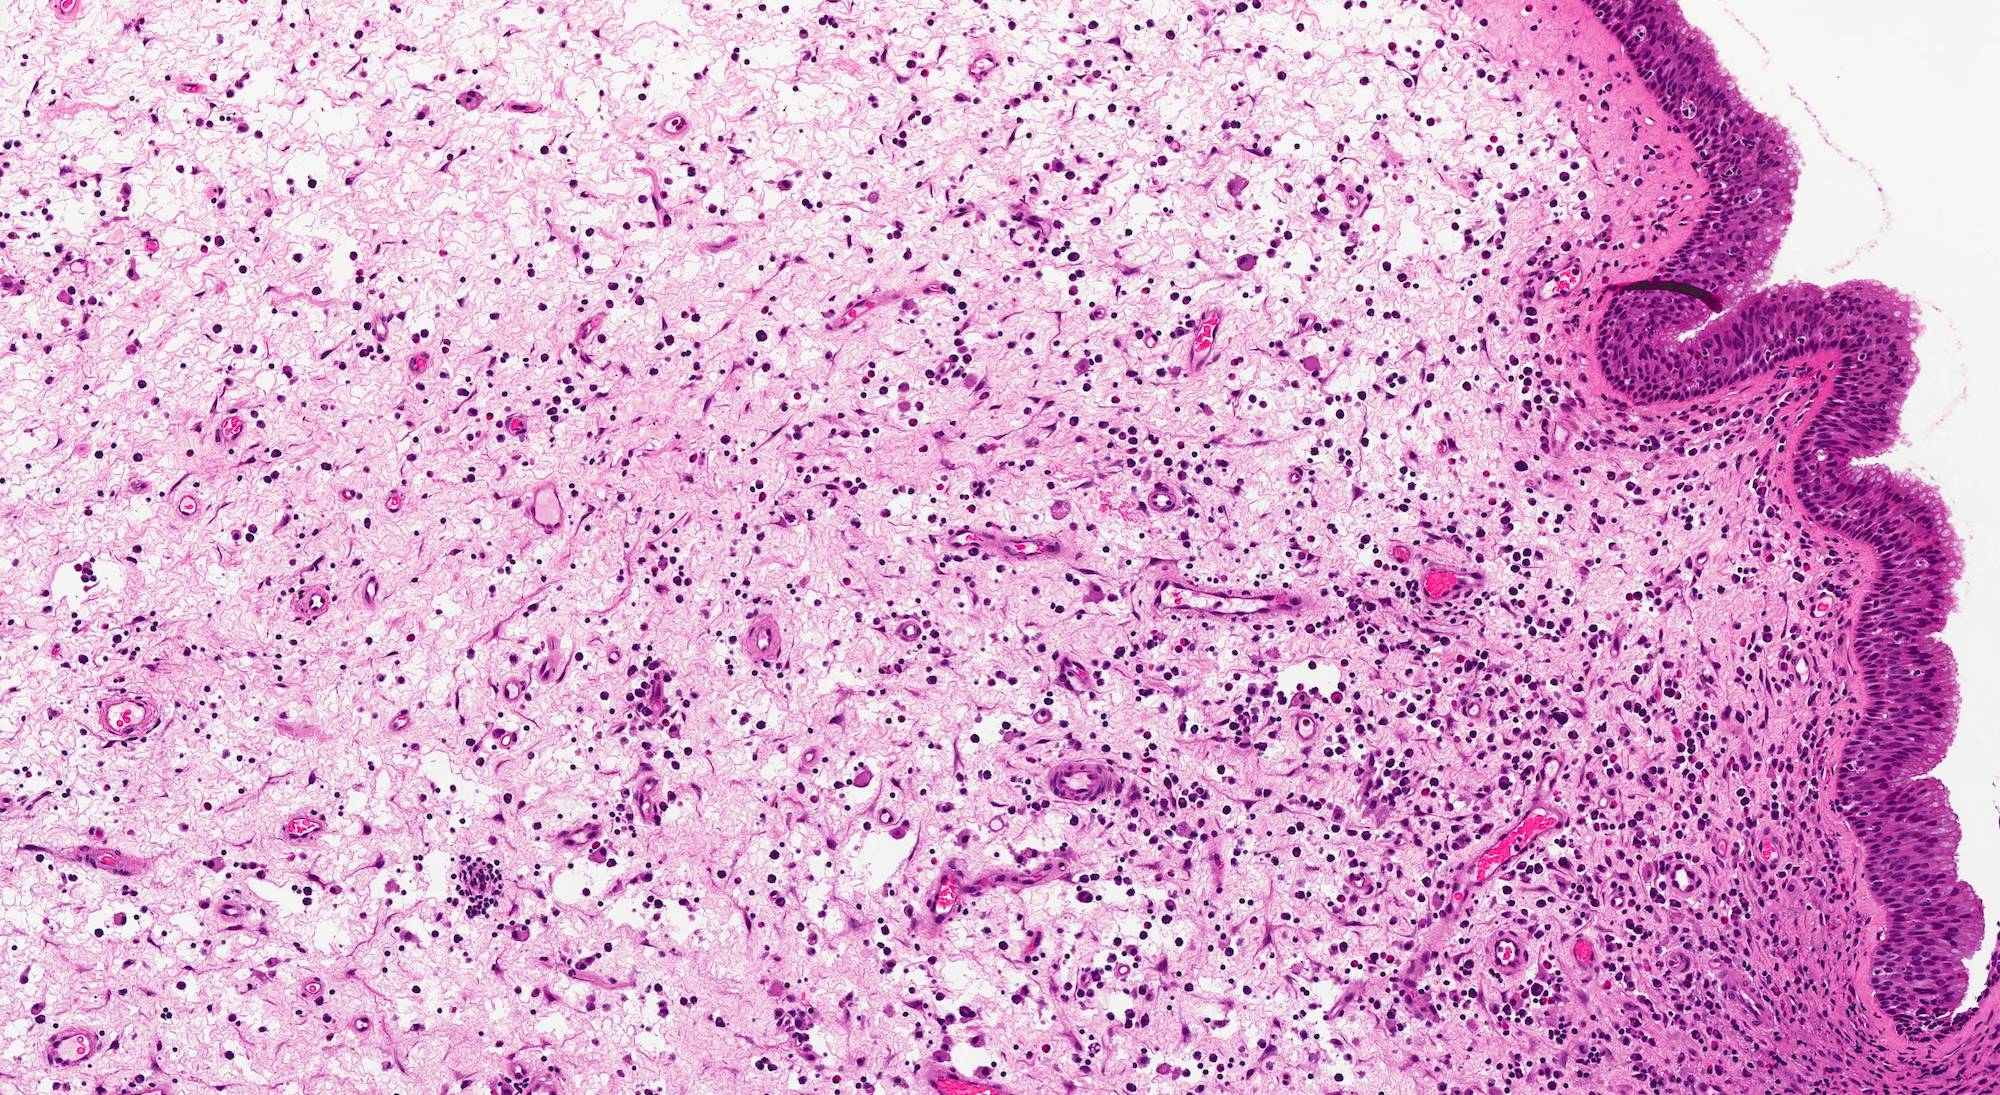

Microscopic (histologic) description

- Edematous, fibrotic or loosely myxoid stroma covered by respiratory epithelium

- Infiltrated by mixed inflammatory cells, including lymphocytes, plasma cells, eosinophils, neutrophils and mast cells

- Surface epithelium can show ulceration or squamous metaplasia

- May have bizarre stromal cells (large and pleomorphic)

- Submucosal glands are decreased or absent

- Concurrent fungal infection may be seen

- Rarely, osseous metaplasia may be present

Microscopic (histologic) images